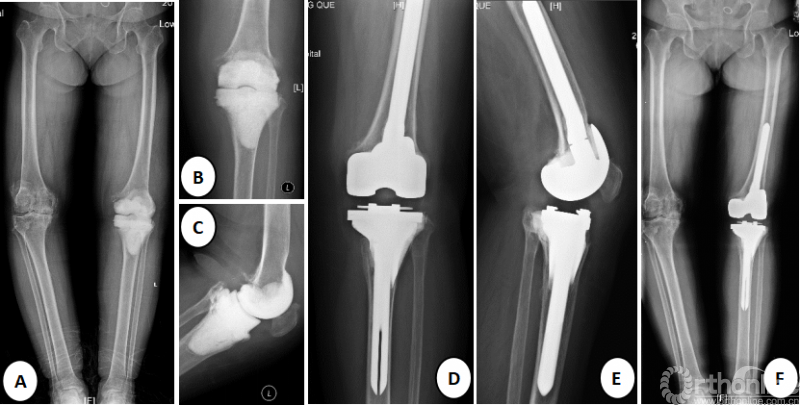

图2.某患者X线片;A、B、C为术前X线片,患者因假体周围感染,已行假体取出及spacer置入术;D、E、F为术后36月随访时X线片,未见假体周围骨折、假体周围感染、假体松动等迹象,术侧下肢力线良好